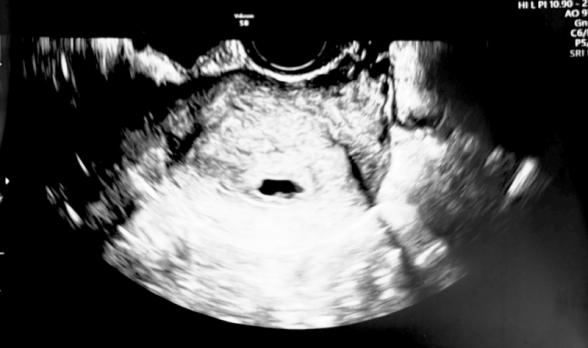

6w4dに健診に行き、胎嚢は確認できたのですが

心拍は確認できませんでした。

先生には胎嚢の形が悪いので

心拍も確認できないし、成長できない卵かもしれない

流産の可能性がある

確かに胎嚢の形が悪いように思いますが